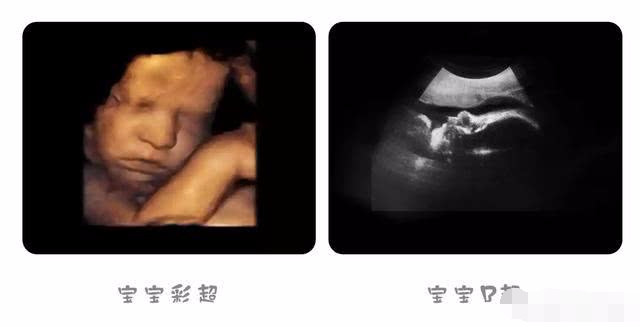

35週超音波錄影 5 30後是3d 高雄正薪醫院 Youtube